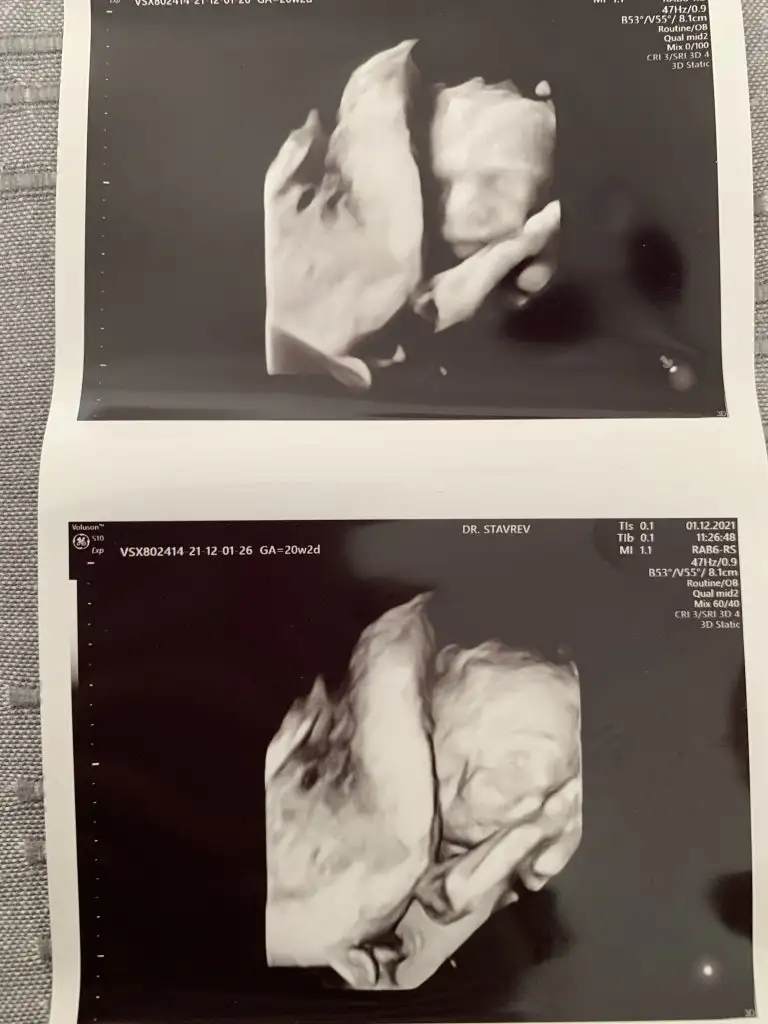

Allah’ım pozlara bakKızlarrrr ben bir güzelle tanıştım geldim ilk kez yüzünü gördümkaşları bile çıkmış dudakları görünüyor galiba aşık oldum boyumuz 20.5 cm , kilomuz 304 gram . Gelişimimiz icin gayet iyi gidiyor dedi beynini kalbini ve diğer organlarını inceledi her şeyin yolunda olduğunu söyledi çok şükür Önümüzdeki hafta detaylı ultrason icin bir başka doktora yönlendirdi , diğer kontrolümüz icin de 3 Ocak tarihini verdi . Bizde haberler böyle cinsiyette herhangi bir değişme var mı diye de sordum bir arkadaşımızın başına gelmişti , ama bize bir prenses geliyormuş kesin olarak tekrar baktı Çekmeyin der gibi nasıl da yüzünü kapatıyor ya onun o ellerini yiyeceğim doğsun da hele o başını kollarına yaslaması Gerçekten aşık oldum ben

Kızlarrrr ben bir güzelle tanıştım geldim ilk kez yüzünü gördümkaşları bile çıkmış dudakları görünüyor galiba aşık oldum boyumuz 20.5 cm , kilomuz 304 gram . Gelişimimiz icin gayet iyi gidiyor dedi beynini kalbini ve diğer organlarını inceledi her şeyin yolunda olduğunu söyledi çok şükür Önümüzdeki hafta detaylı ultrason icin bir başka doktora yönlendirdi , diğer kontrolümüz icin de 3 Ocak tarihini verdi . Bizde haberler böyle cinsiyette herhangi bir değişme var mı diye de sordum bir arkadaşımızın başına gelmişti , ama bize bir prenses geliyormuş kesin olarak tekrar baktı Çekmeyin der gibi nasıl da yüzünü kapatıyor ya onun o ellerini yiyeceğim doğsun da hele o başını kollarına yaslaması Gerçekten aşık oldum ben